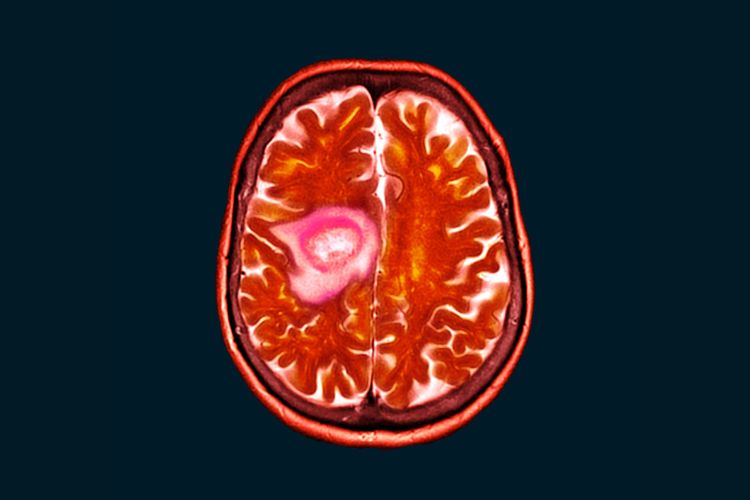

MR koristi magnetno polje i radio talase za detaljne slike tela, bez zračenja. Traje 30-60 minuta i efikasna je za otkrivanje anomalija mozga, tumora, srčanih problema i više.

Magnetna rezonanca glave je bezbolna i detaljna metoda snimanja mozga, koristi se za dijagnostiku neuroloških tegoba. Priprema je jednostavna, a rezultati brzo dostupni.